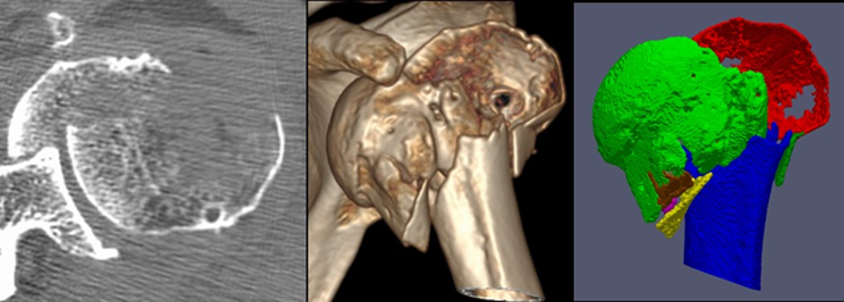

Seventeen patients with proximal humeral fractures and a preoperative CT scan were included in this retrospective study. The CT scans were semi-automatically segmented, indicating every fracture fragment in a different color. Fracture classification ability of 21 orthopedic residents and 12 experienced shoulder surgeons was tested. Both groups were asked to classify the fractures using 3 different modalities (standard slice-wise CT analysis, conventional 3D CT reconstruction, and 3D segmented model) into three different classification systems (Neer, AO and LEGO). All participants were able to classify the fractures significantly better using the 3D segmentations (94% correct answers on average) compared with the conventional 3D reconstructions (54%) and with the standard slice-wise CT analysis (35%) into the three classification systems, p<0.01. Both observer groups achieved significantly worse classification accuracy in the LEGO system compared to the two others.